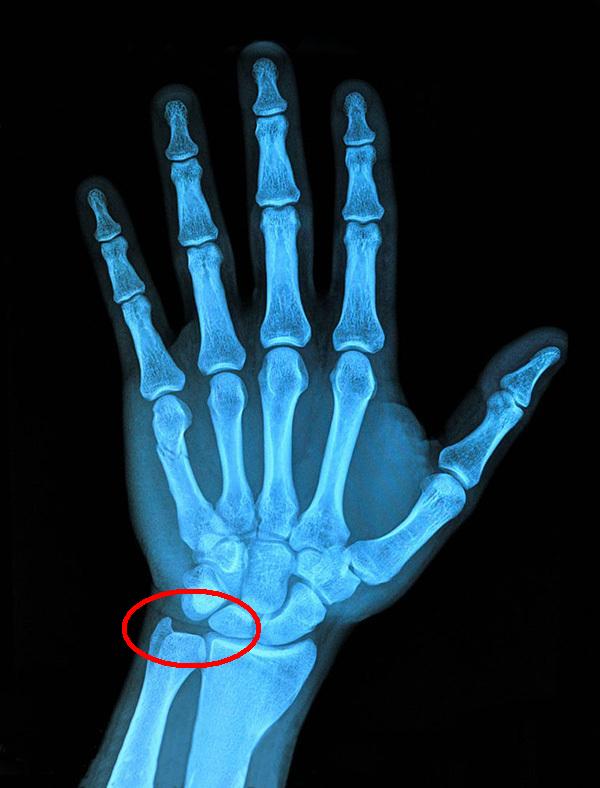

从腕关节受伤的具体部位来说,主要分为大拇指一侧的腕管综合征、桡骨茎突腱鞘炎,小拇指一侧的三角盘软骨损伤三种。

3.三角盘软骨损伤,一般为慢性损伤,也有急性损伤的可能。损伤的主要原因是腕关节的三角盘软骨处反复受到大重量挤压和拉伸、腕关节反复弯折和弯折时受力不均。症状较轻时可保守治疗,严重时需要手术治疗。